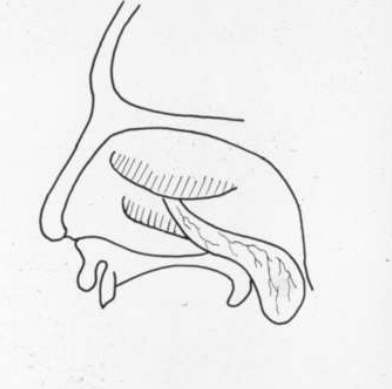

pólipo de Killian o antrocoanal características morfológicas (dónde y cómo se presenta y extensión)

dd de pólipo de Killian

al ser unilateral–> neoplasia nasosinusal